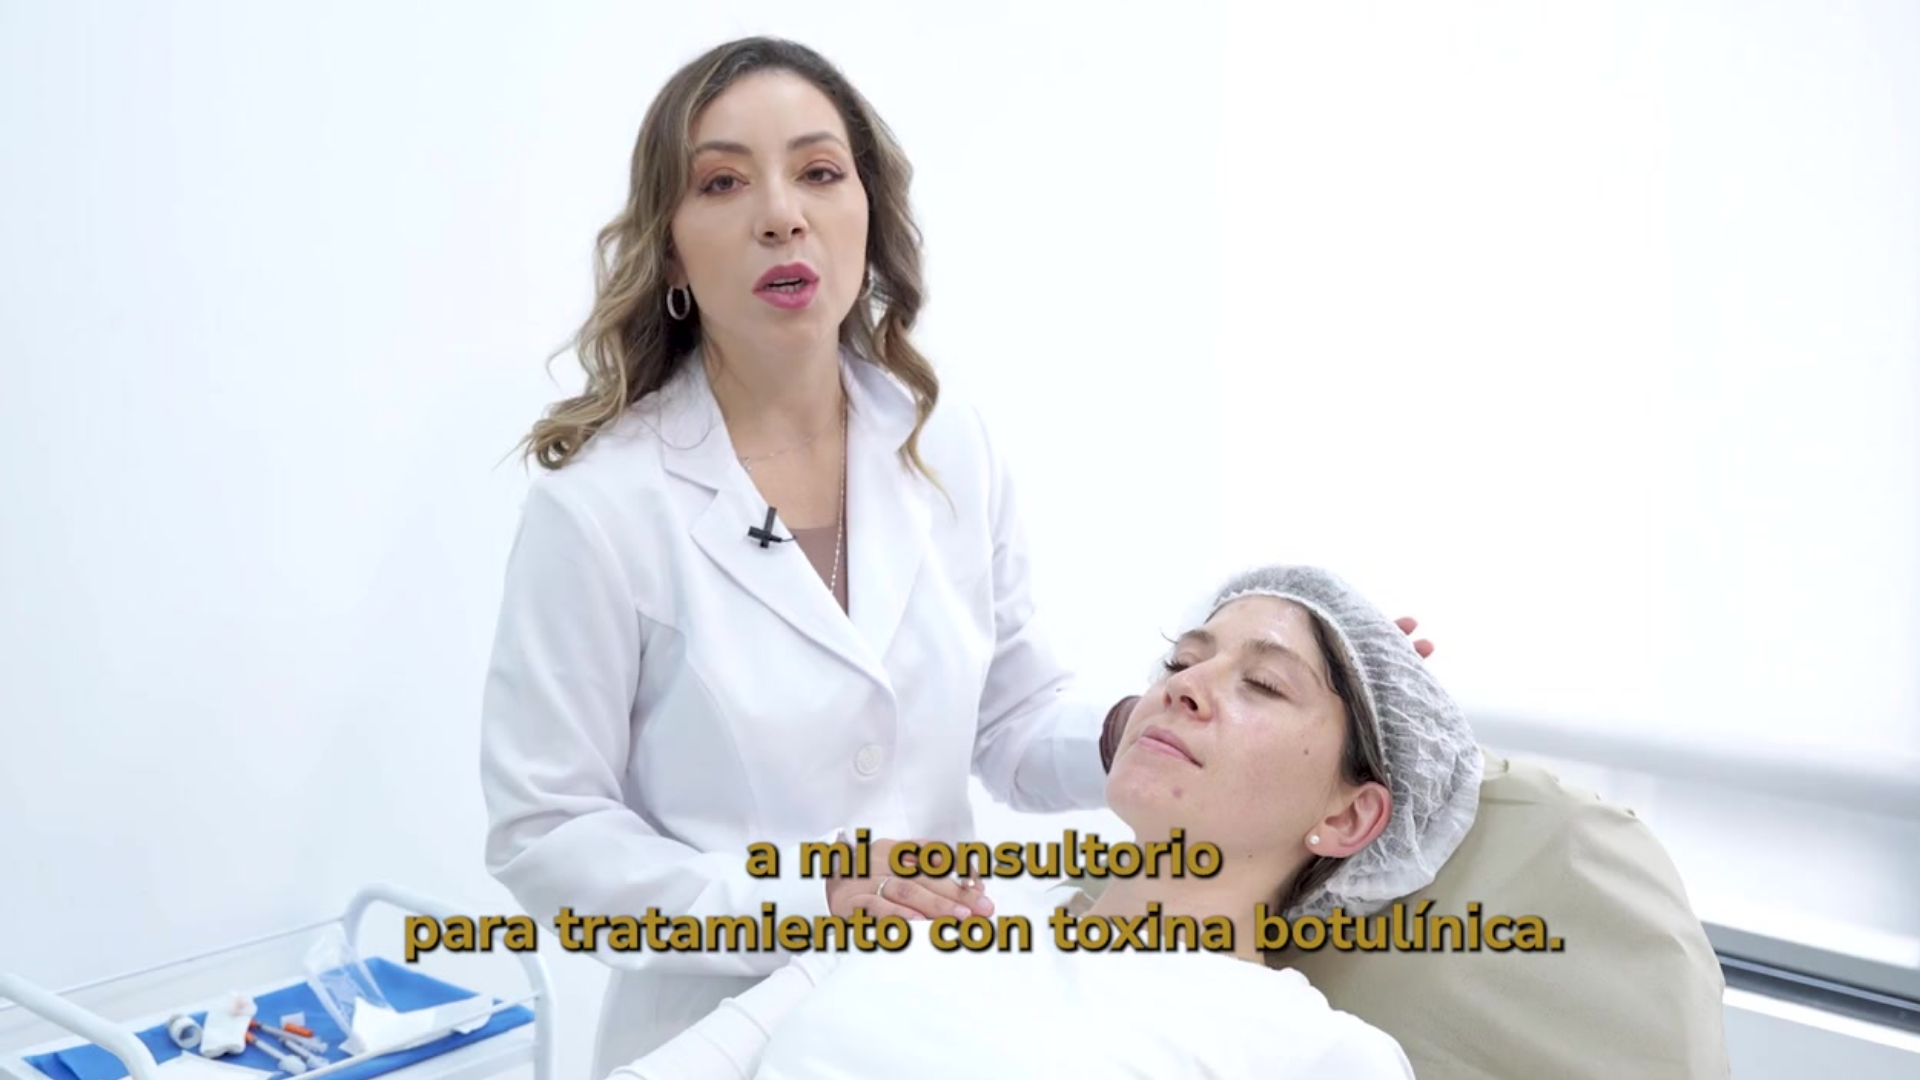

Somos expertosen el cuidado y tratamiento médico, quirúrgico y estético de la piel de hombres, mujeres, niños y personas de la tercera edad.

Tratamientos Dermatológicos

Dermatológia Estética